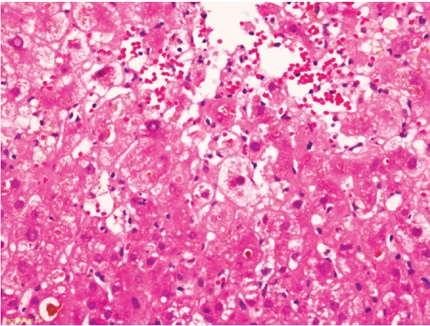

Histológicamente, se caracteriza por edema celular o balonización, necrosis aislada con formación de cuerpos acidofílicos o necrosis masiva acompañada de agregados de neutrófilos y colestasis hepatocanalicular de localización perivenular (zona 3), dada la mayor susceptibilidad de esta región a los eventos isquémicos, los cambios se hacen evidentes en las primeras 48 horas después del trasplante (Figuras 1 y 2). Cuando se toman biopsias en tiempo cero (0), o posreperfusión, son más prominentes los agregados de células inflamatorias polimorfonucleares neutrófilos. En casos severos, disminuye la inflamación y aumenta la necrosis, lo que compromete todo el ácino (panacinar) (13).

Menos frecuentemente pueden observarse necrosis en región periportal o infartos subcapsulares. Cuando hay donante con hígado graso, la lesión de reperfusión favorece la ruptura de hepatocitos, lo que libera glóbulos de grasa, que se quedan atrapados en los cordones de hepatocitos y causan obstrucción, semejando sinusoides dilatados o lipopeliosis, los cuales pueden migrar al pulmón causando embolia grasa. El pronóstico de esta condición depende directamente del porcentaje de parénquima con necrosis (14). Se incluyen en el diagnóstico diferencial el rechazo humoral, rechazo celular y complicaciones quirúrgicas, en especial de anastomosis vascular o de la vía biliar. La colestasis de presentación muy temprana también puede deberse a injertos pequeños para el donante (small-for-size), casos en los que el edema celular es muy prominente y de localización no solo perivenular sino que puede ser difusa o panacinar.